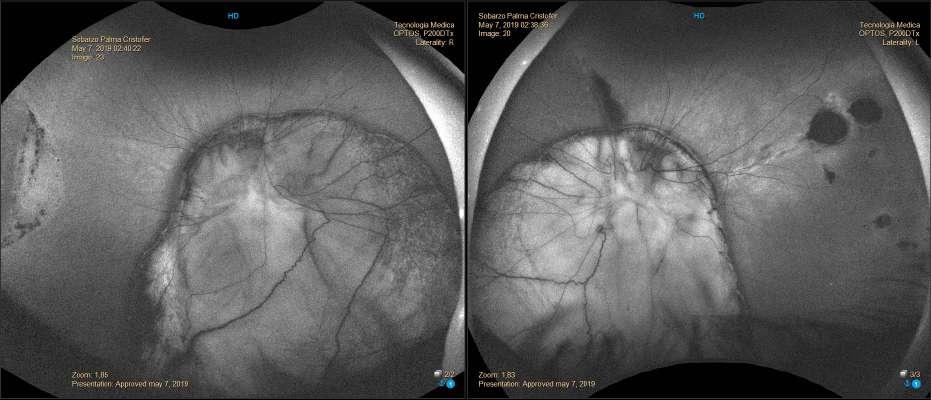

ü Hombre 19 años portador de Leucemia linfatica aguda diagnosticada el 2016, es tratado ese mismo año con trasplante alogénico, sin embargo 4 meses posterior al trasplante sufre una recaída leucémica. Desde entonces el paciente se ha mantenido en QMT sistémica paliativa

ü El año 2017 el paciente evoluciona con enfermedad injerto contra huesped y el 2018 con meningitis leucémica

ü El año 2019 consulta en el policlínico de oftalmología del Hospital del Salvador por disminución de AV ODI de 7 dias evolución, asociado a sensación de cuerpo extraño.

Examen Físico

ü AV con CAE: 20/70 OD y 20/60 OI

ü PIO normal bilateral

ü DPAR en OD

ü Motilidad ocular conservada.

ü BMC: Puntata extensa como consecuencia de efectos adversos producidos por la QMT (Imagen A y B) A